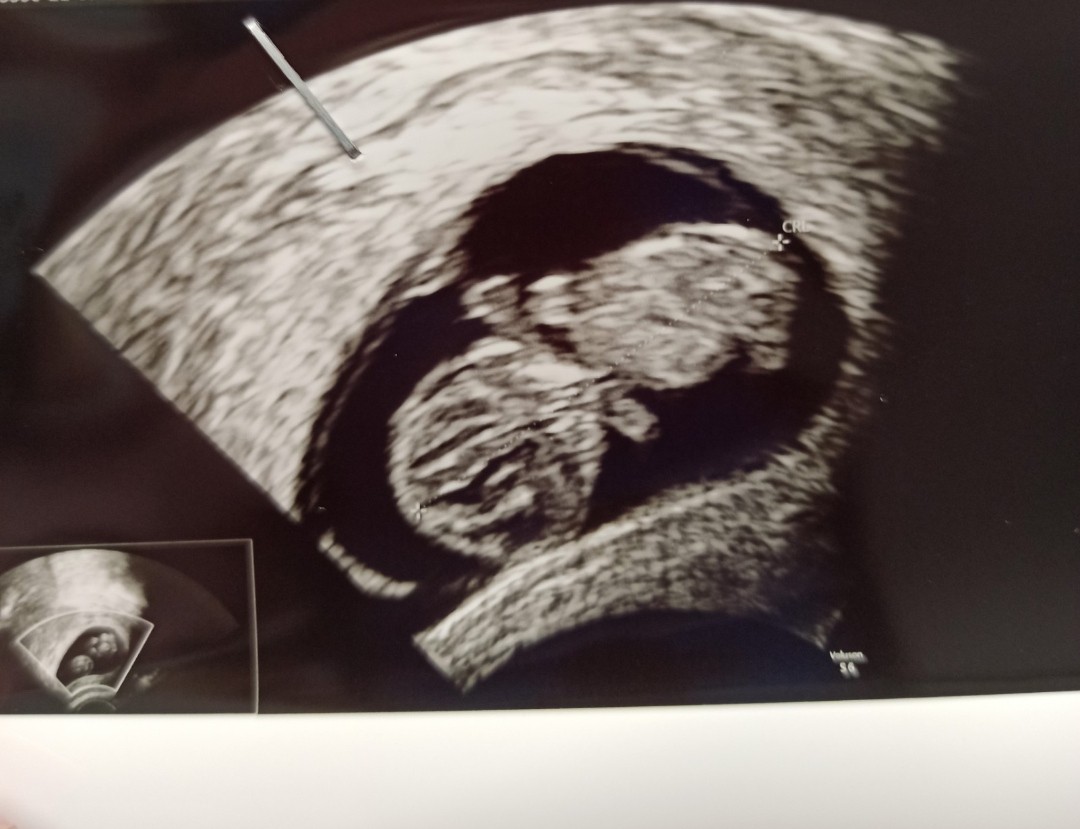

We wtorek byłam na USG i już maleństwo więcej widać